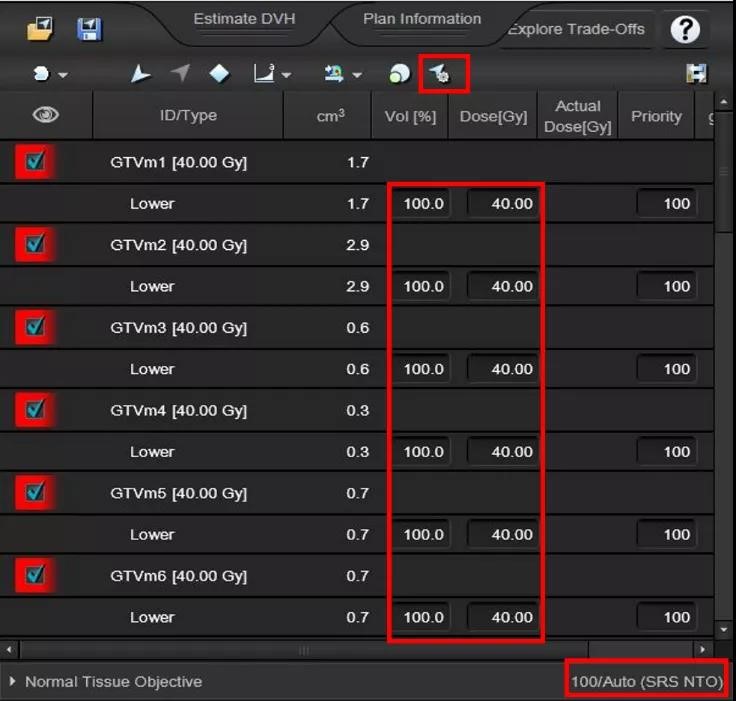

优化

1、自动添加靶区Lower优化条件

2、ALDO (Automatic Lower Dose Objective)自动设置所有靶区都得到98%体积的覆盖,避免多靶点计划不同靶点剂量覆盖不一致

3、SRS NTO:靶区外剂量跌落更加快速